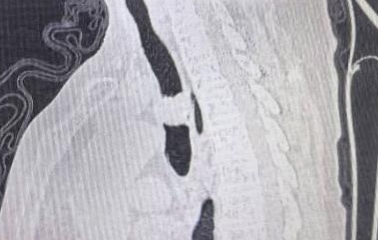

术后

原发性气管肿瘤是指原发于第一气管环以下至隆突以上范围内的气管肿瘤、多起源于气管后壁的膜部与软骨交界处的黏膜上皮和腺体,为呼吸系统的少见病症。成人主气管平均长度12cm,一般手术切除一期吻合最大长度不超过5cm。该患者主气管长度仅10cm,术中切除气管长度4cm,上、下切缘各2mm,切除总长度达4.4cm,近主气管一半长度,术中配合双侧肺门松解最大限度保证气管切除长度、最大限度降低气管吻合口张力,术后未进行下颌前胸减张缝合,大大提高患者术后舒适感加速患者康复。